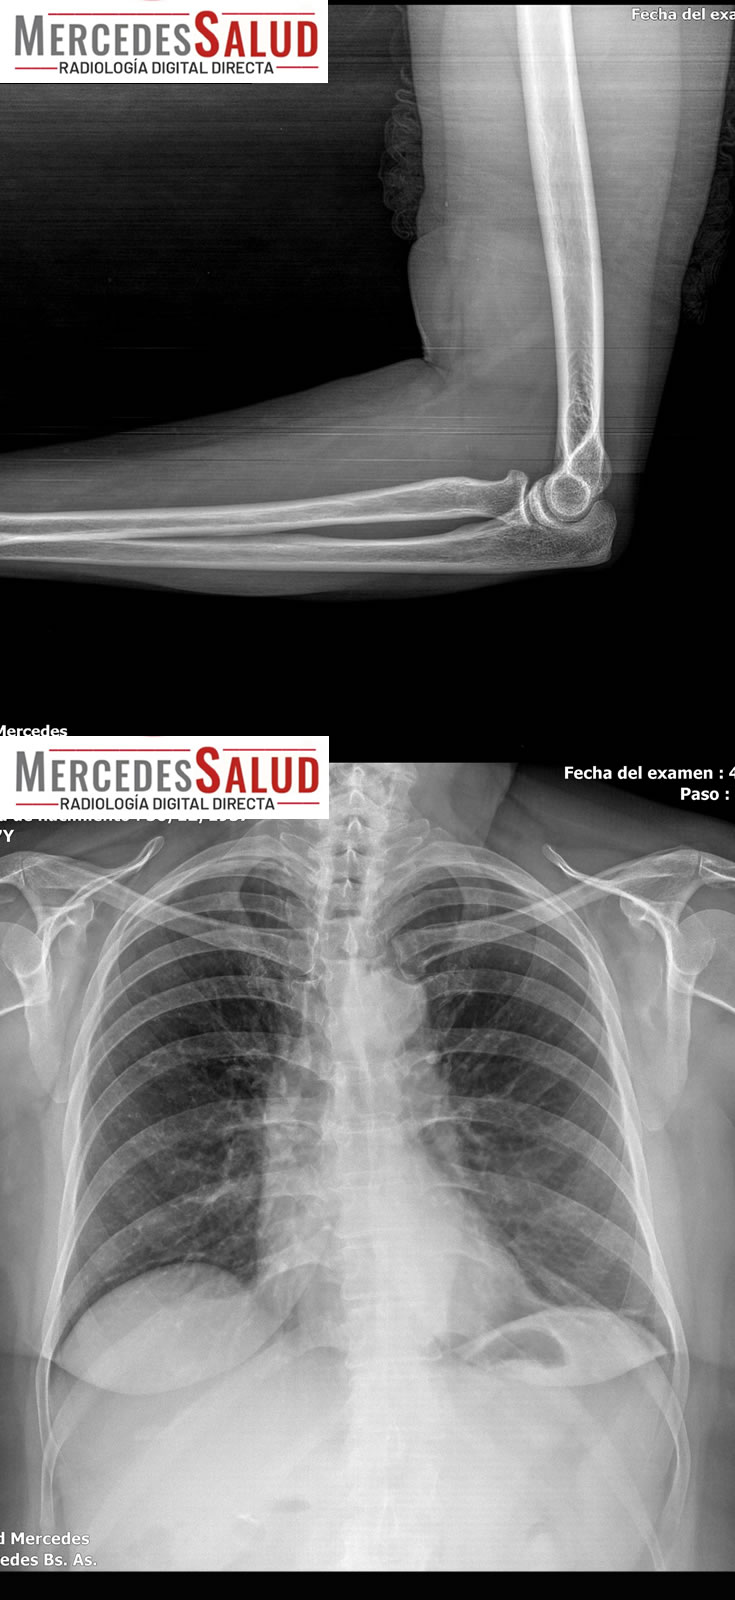

Amplio espectro de estudios

Además del tomógrafo dental, que realiza panorámicas dentales y tomografías, y permite realizar laminografías de la articulación temporomandibular (ATM) y placas de macizo facial para casos como fracturas, el servicio también ofrece estudios especializados como espinogramas y mediciones de miembro inferior con el equipo Pimax. Estos estudios de alta calidad son muy requeridos por traumatólogos de la ciudad y zonas aledañas. La calidad de imagen es tal que, según el Lic. Quiroga, pacientes de ciudades vecinas viajan a Mercedes para ser atendidos.

Un punto fundamental a destacar es la baja dosis de irradiación que reciben los pacientes. Al tratarse de equipos modernos, la exposición es mínima, un factor que es complementado con estrictas medidas de seguridad, incluyendo el uso de protección personal plomada (chaleco y tiroides) para quienes asisten.